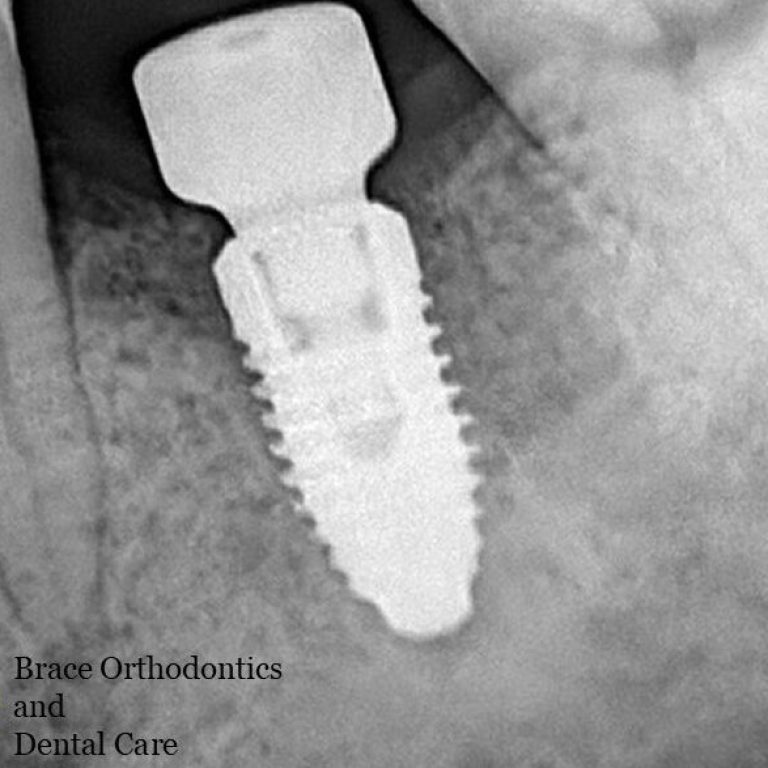

Best Dental Implant Clinic in Dhaka at Banani Take Another Chance to Smile and Visit best dental implant clinic in Dhaka Looking for best dental implant … by rahman.smm@gmail.comJanuary 5, 2026